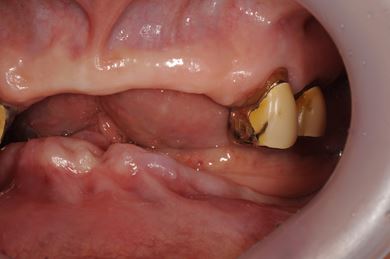

インプラント治療+オーバーデンチャー

| 性別/年齢 | 女性 / 85歳 | ||||||||||||||||||||||||||||||||

| 主訴 | 義歯の調子が悪い。 | ||||||||||||||||||||||||||||||||

| 治療方針 | 下顎に2本インプラントを埋入し、アタッチメントをつけて、オーバーデンチャーを装着し、はずれにくく、安定した義歯を装着する。 | ||||||||||||||||||||||||||||||||

| 治療内容 | インプラント2本(テンポラリーインプラント)、アタッチメント、コバルトクロム床オーバーデンチャー | ||||||||||||||||||||||||||||||||

| 総治療費 | 1,540,350円 | ||||||||||||||||||||||||||||||||

| 治療期間 | 5ヶ月 |